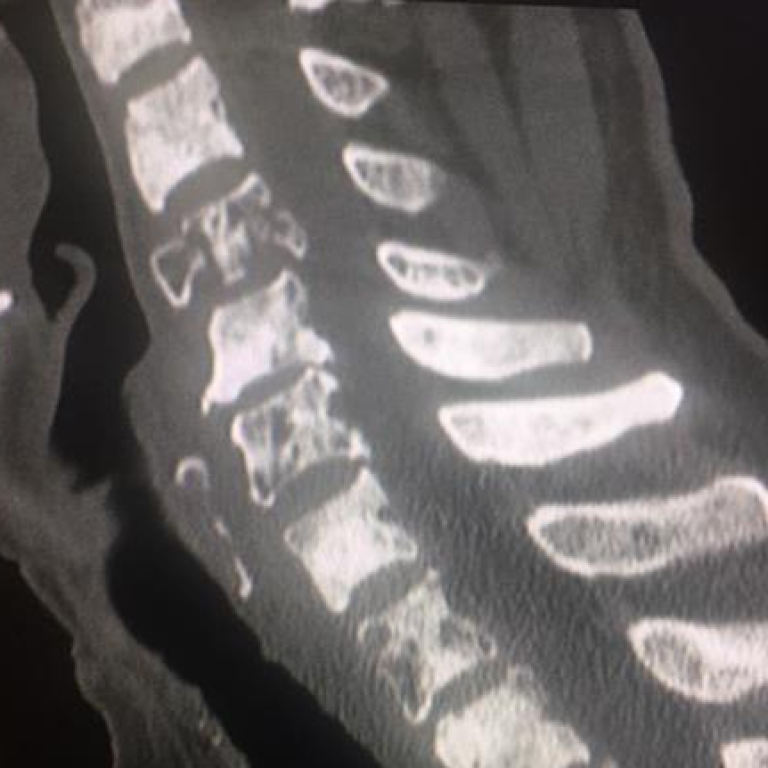

Fisiatra Serendipiti nella Cervicalgia e Lombalgia Comunemente si pensa che cervicalgia e lombalgia siano due banalissimi disturbi… by exodiadmin13 Gennaio 2024